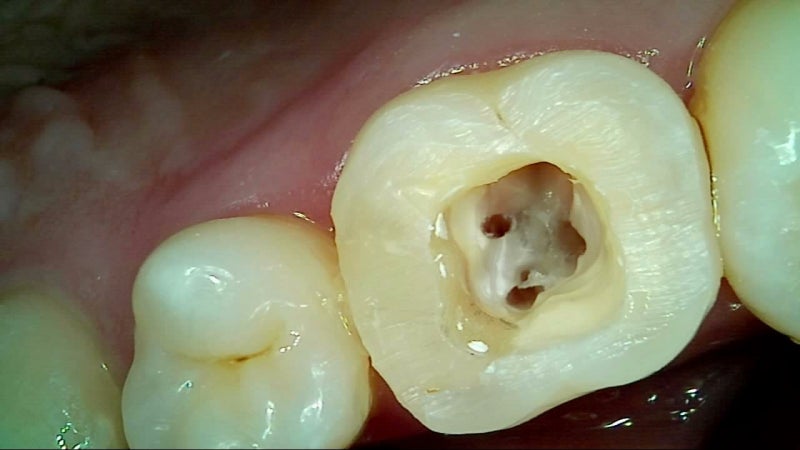

씹을 때 통증, 푹 꺼지는 느낌 등이 느껴진다면 크라운 손상 가능성을 의심해야 합니다. 특히 신경치료한 치아가 노출되었다면 즉시 치과를 방문해야 합니다.

- X‑ray 및 육안 진단 → 상태 확인

- 재접착 가능 시 임시/영구 접착 → 안 되면 새 크라운 제작

- 임시 크라운 장착 후 최종 크라운 장착 (1~2주 소요)

아니요. 노출된 치아 조직이 세균에 감염될 수 있어 빠르게 치과를 방문해야 합니다.